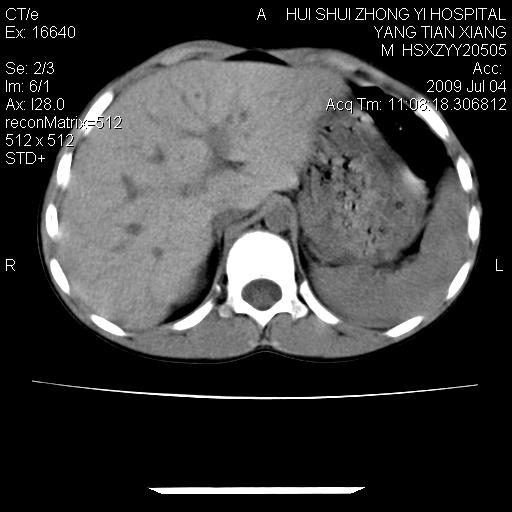

肝右叶胆管内见条状高密度影,脾脏增大,双肾上腺无异常;右肾正常结构消失,其实质内见类圆形低密度灶,ct值范围0-6hu,界清,右输尿管全程伴行多发低密度灶,界清,膀胱壁增厚,腹盆腔未见确切肿大淋巴结。

考虑:1、肝内多发胆管结石并肝内胆管扩张。2、右肾、输尿管多发脂肪瘤,多发平滑肌瘤?建议ct增强检查。4、膀胱壁增厚。

1)考虑右侧巨输尿管畸形。2)肝内胆管多发性结石。3)脾大。

右侧巨输尿管并神谕积水,左肾代偿性肥大,脾大,肝内胆管多发结石并胆管扩张。